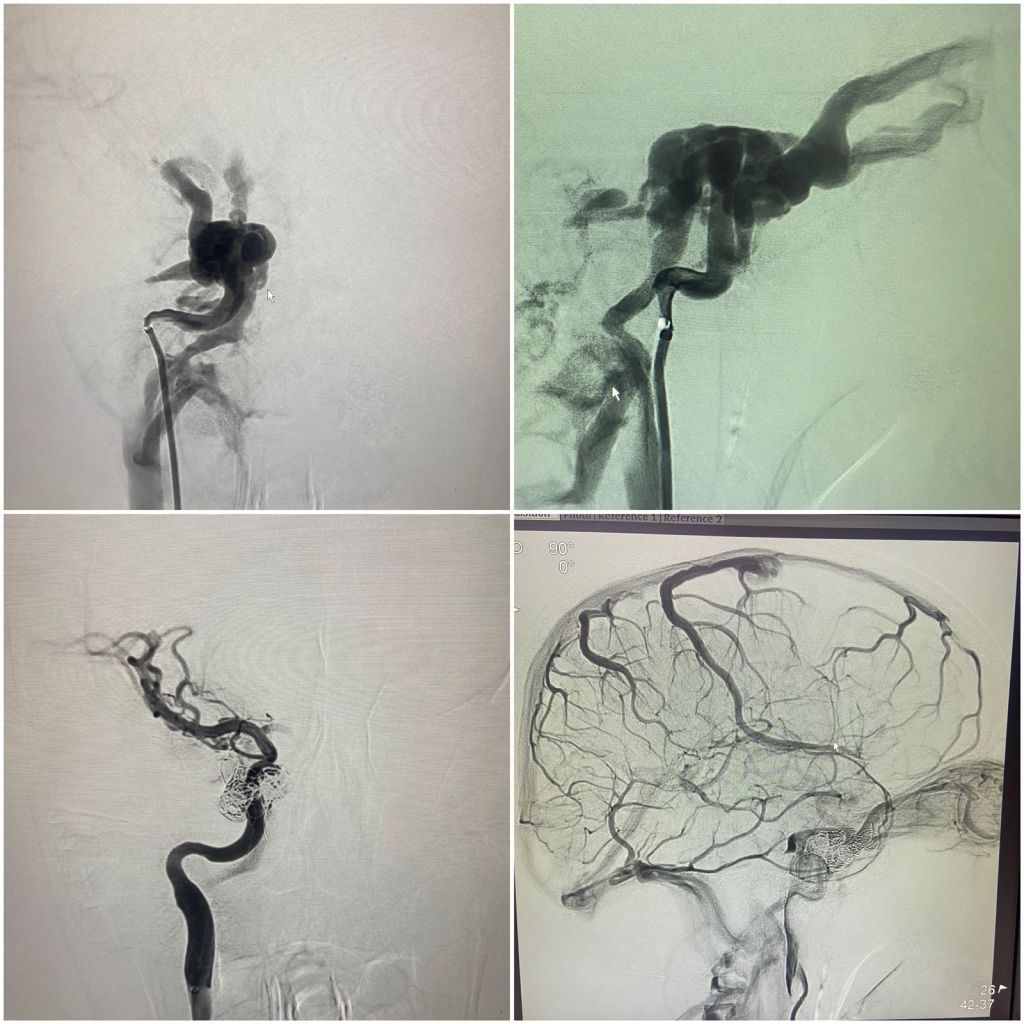

एम्स,ऋषिकेश की कार्यकारी निदेशक एवं सीईओ प्रोफेसर (डॉ.) मीनू सिंह के निर्देशन में संस्थान के इंटरवेंशन रेडियोलॉजी विभाग में उच्च तकनीकी वाले न्यूरो इंटरवेंशन जैसे कैरोटिड स्टेंटिंग (खून की नस में सिकुड़न ) ए.वी.एम व ए.वी.एफ( खून की नसों का गुच्छा) , स्ट्रोक (लकवा) एन्यूरिजम (खून की नसों का गुब्बारा व नसों का फटना) समेत कई अन्य तरह की बीमारियों का बिना किसी चीरफाड़ के इलाज उपलब्ध है। बताया गया है कि यह उपचार एम्स अस्पताल में मरीजों को बीते आठ महीने से आयुष्मान भारत योजना के तहत निशुल्क दिया जा रहा है।

संस्थान में यह कार्य दिल्ली एम्स से प्रशिक्षित एवं वर्तमान में एम्स ऋषिकेश के इंटरवेंशन रेडियोलॉजी विभाग (भूतल बी- ब्लॉक) में कार्यरत सहायक आचार्य डॉ. बी.डी. चारण (डी.एम. न्यूरोइंटरवेंशन) द्वारा मरीजों में इस तरह की बीमारियों के उपचार को अंजाम दिया जा रहा है।

विषय विशेषज्ञ डॉ. बी.डी. चारण ने बताया कि विभाग की डीएसए लैब (पांचवीं मंजिल ) में उपचार की यह प्रक्रिया एनेस्थीसिया विभाग के सहयोग से संपन्न की जाती है, जिसमें अन्य विभागों जैसे जेरियाट्रिक मेडिसिन, ईएनटी, नेत्र विभाग, न्यूरोसाइंस व मेडिसिन आदि का भी योगदान रहता है।

डॉ. चारण के मुताबिक इस विधि के तहत जांघ की खून की नस में 2 एमएम का पाइप डालकर ब्रेन तक पहुंच बनाई जाती है, उसके बाद बीमारी का बिना चीरफाड़ किए इलाज किया जाता है। उन्होंने बताया कि चूंकि इस उपचार में चीरफाड़ नहीं किया जाता है, लिहाजा मरीज को अस्पताल अथवा आईसीयू में निहायत कम समय तक ही रुकना पड़ता है और मरीज की जल्दी छुट्टी कर दी जाती है।